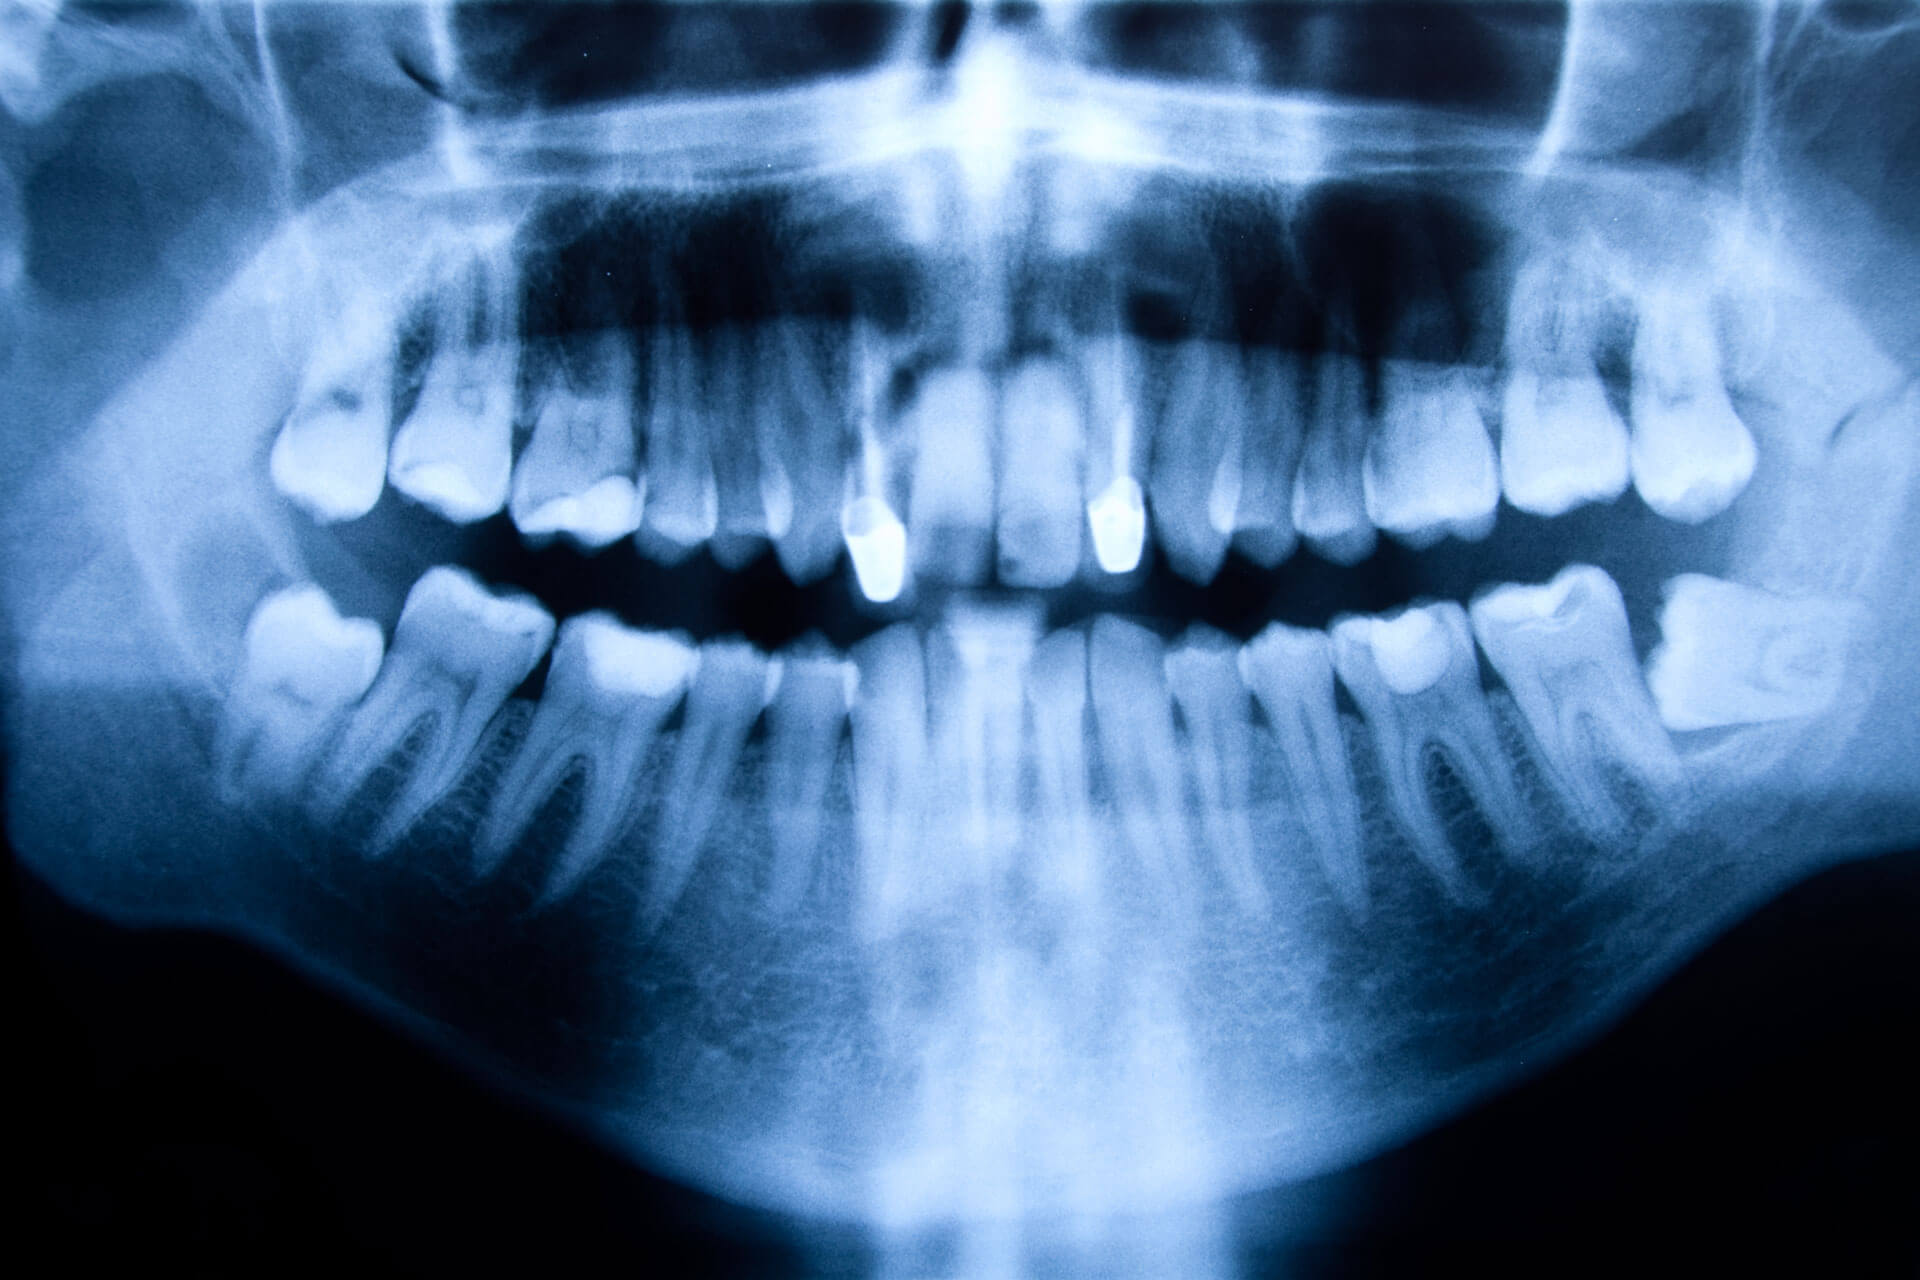

Ante la sospecha de un quiste, el dentista tomará radiografías de la boca a fin de determinar la localización exacta, el tamaño, el estado del diente que lo origina y las estructuras cercanas comprometidas. A veces, también puede solicitar otras pruebas complementarias, como la punción o aspiración del quiste para estudiar la naturaleza de sus células en el microscopio.

- Reabsorción de las raíces de los dientes próximos al quiste (esto se observa con radiografías dentales).